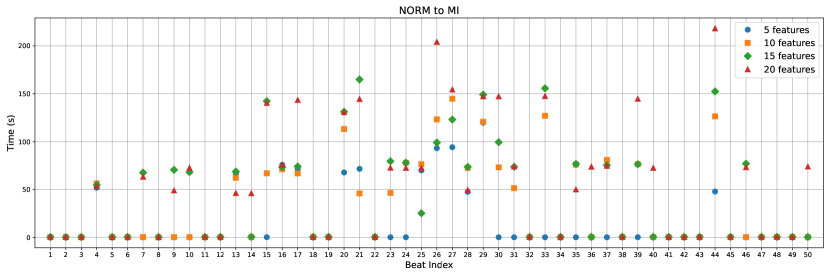

Through our experimental investigations, we discovered that utilizing 19 features is sufficient for extracting counterfactual instances. A lesser number of features is preferable for counterfactuals as it yields better and more reasonable explanations. To conduct a comprehensive assessment of counterfactuals, we generated distinct scenarios involving sets of 5, 10, 15, and 20 features. This evaluation encompassed considerations such as the time taken for generation (refer to Appendix Figure C.6 and C.7) and a comparative analysis of the most influential features affecting the outcomes. The F1 scores for each feature set are as follows: 81.40% for 5 features, 83.50% for 10 features, 85.83% for 15 features, 86.59% for 20 features, and 88.47% for 97 features.

The generation time exhibits variations based on the feature count. When altering from NORM to MI (Appendix Figure C.6), the generation times are as follows: for the case of 5 features, it takes 17.71 ± 33.0 seconds; for 10 features, it takes 35.35 ± 45.62 seconds; for 15 features, it takes 46.86 ± 53.35 seconds; and for 20 features, it takes 58.06 ± 61.8 seconds. Notably, there is a consistent escalation in both the average and standard deviation of generation times with an increase in the feature count.

However, when considering the change from MI to NORM (Appendix Figure C.7), the generation times exhibit different behavior: for 5 features, it takes 73.2 ± 106.46 seconds; for 10 features, it takes 132.64 ± 259.36 seconds; for 15 features, it takes 111.94 ± 121.75 seconds; and for 20 features, it takes 127.48 ± 129.02 seconds. In this case, the observed pattern in generation time does not follow the same trend as seen in the previous scenario. Table 2 demonstrates that the MI to NORM transition poses greater challenges for the model. This is evident from the observed increase in overall counterfactual generation times, which can be attributed to this particular transition being more demanding in optimization process.

To make the durations more conspicuous, you can see the elapsed times for sample 50 beats with 5, 10, 15, 20 feature counts in Figure C.6 and C.7.